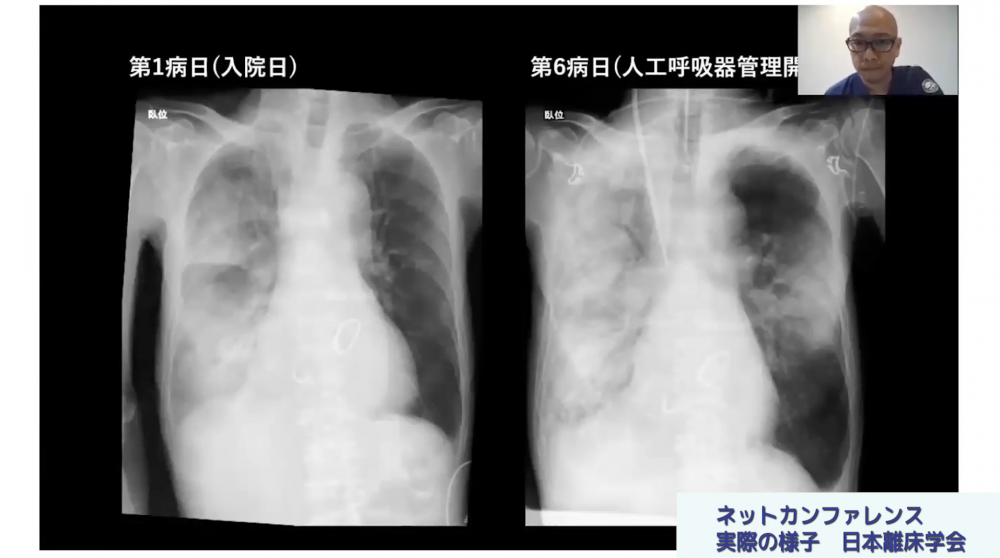

実際のカンファレンス映像を見ていただくことでより伝わるかと思いますが、私などが進行役を担い、相談者からの症例提示に対してデータやレントゲン写真などを画面共有を使いながら情報を共有、意見交換を進めます。